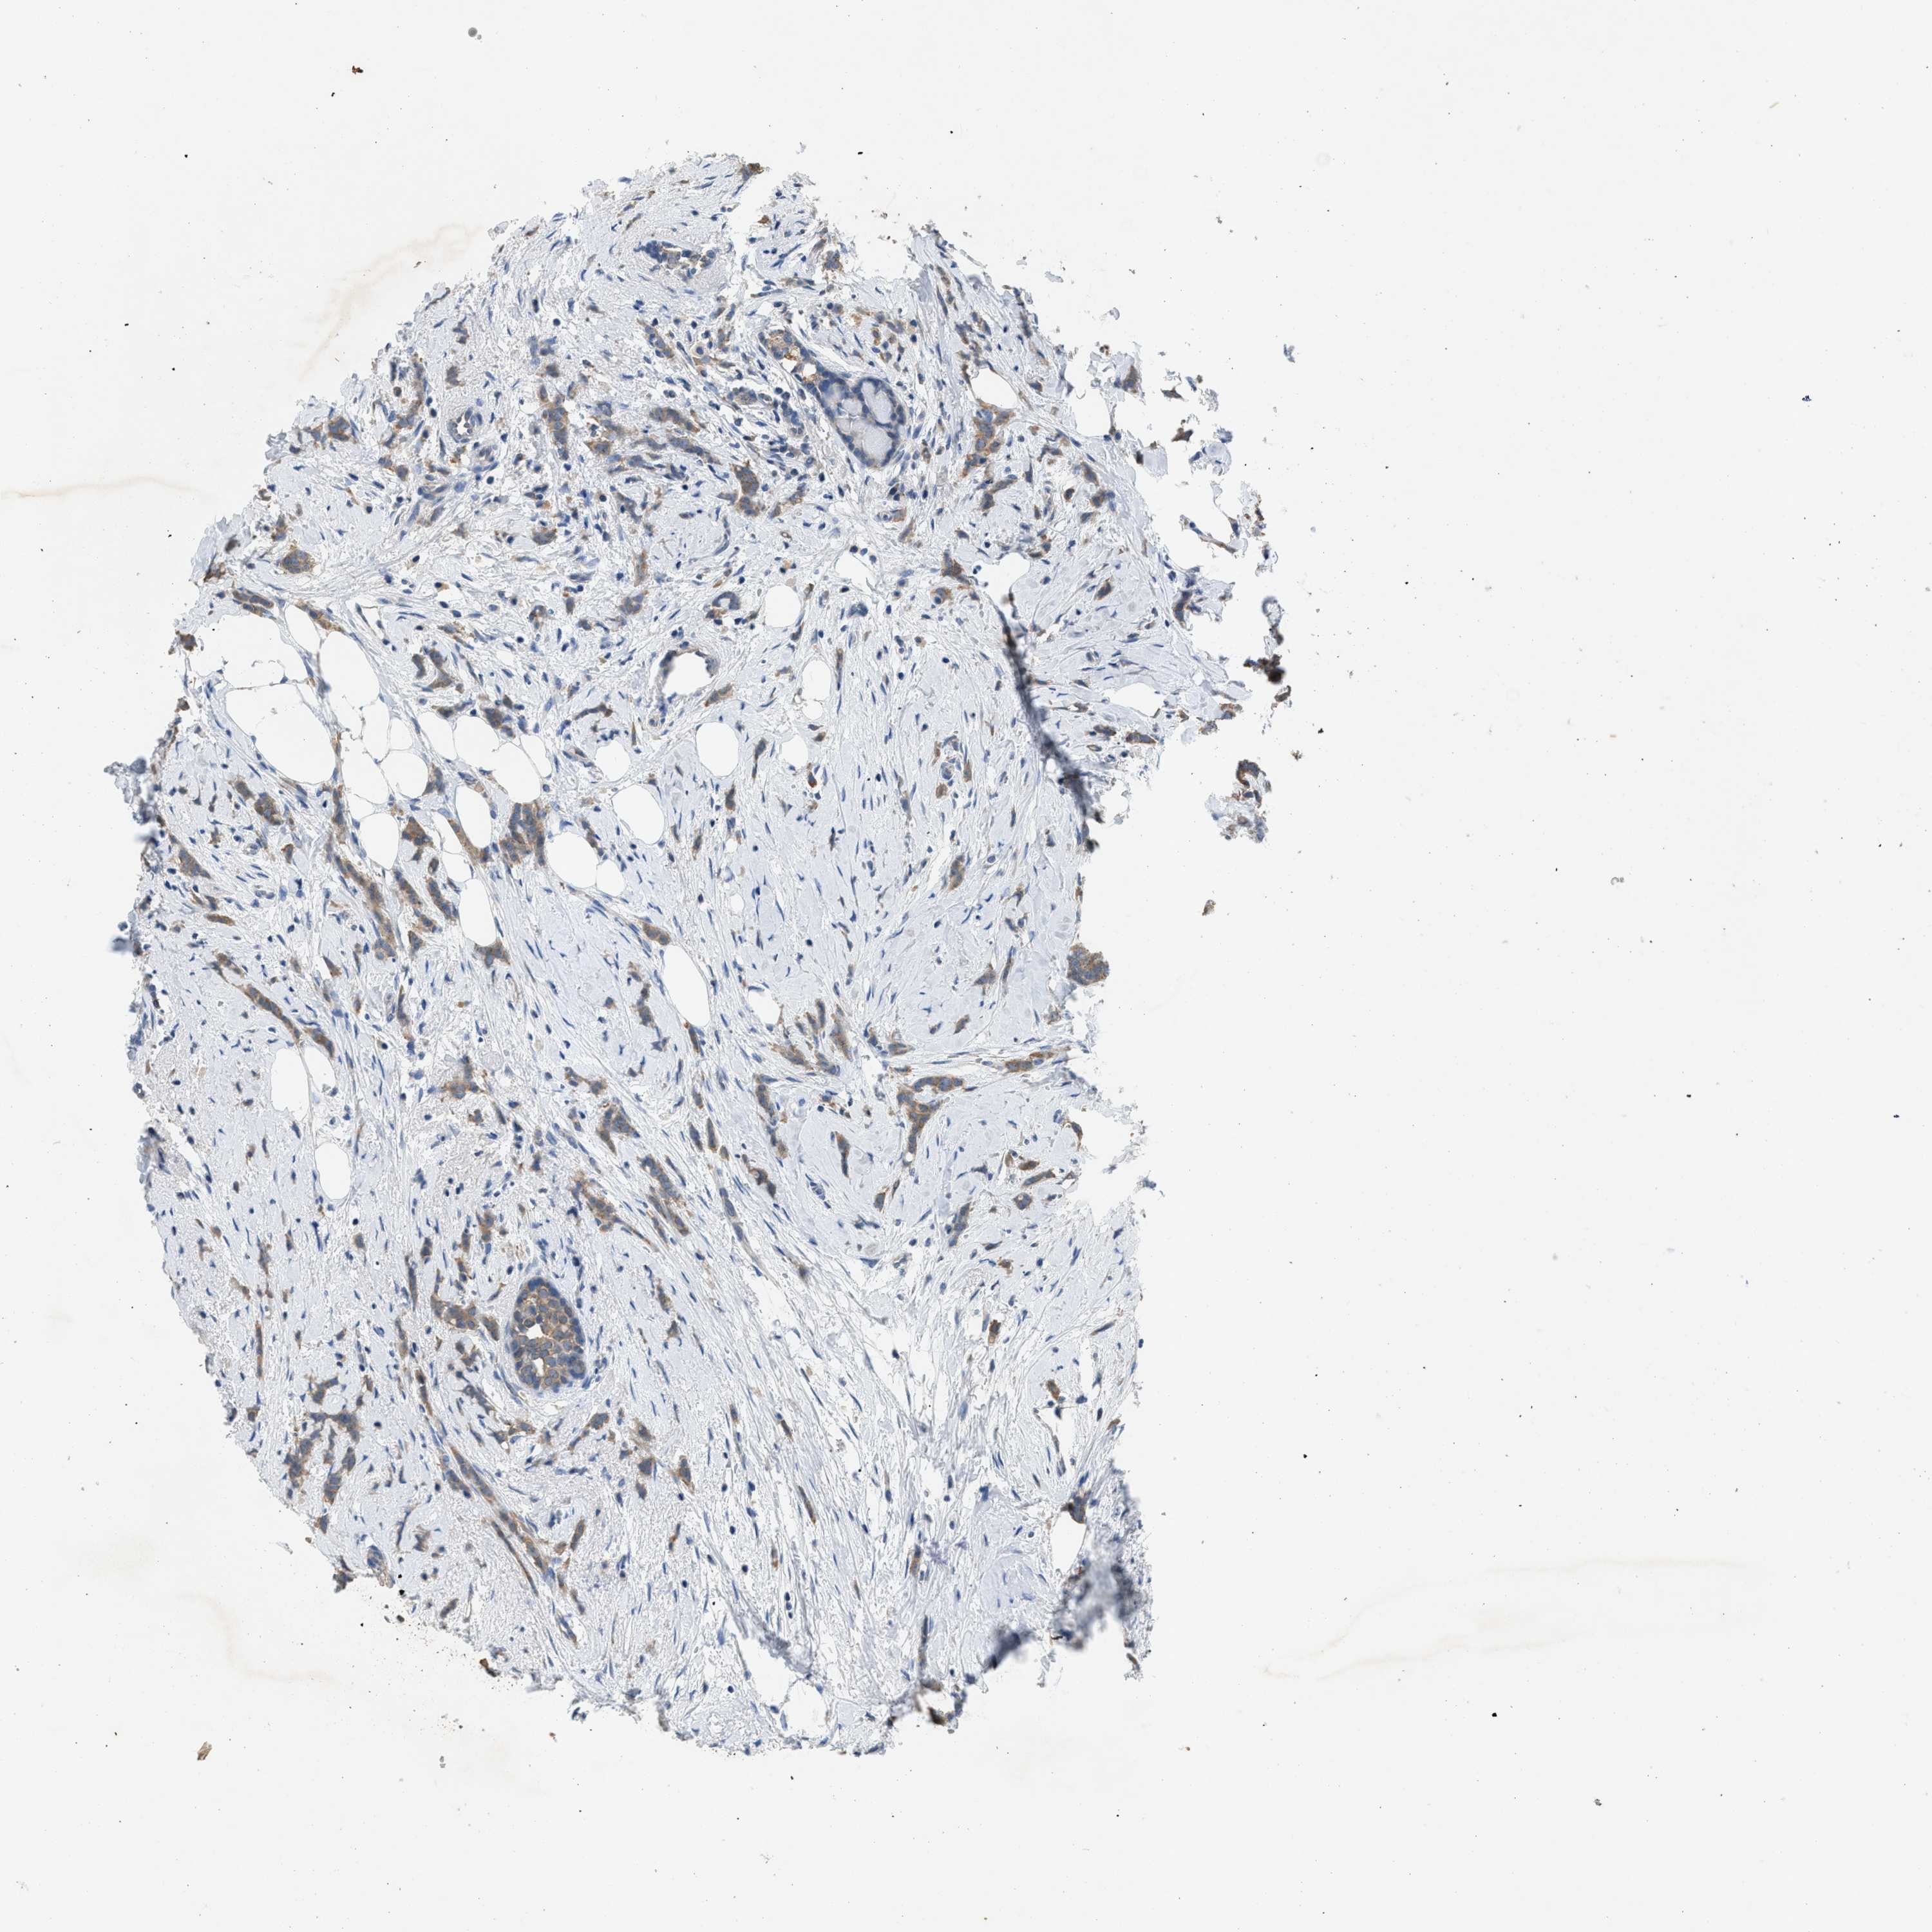

CANCER BREAST CANCER Show tissue menu

BRCA TCGA BRCA VALIDATION PROTEIN EXPRESSION